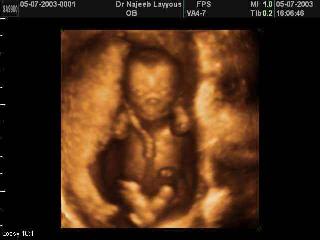

“As for abortion, it is what it is. The fetus is what it is. In my mind, the one who gets to decide that value is the woman who’s pregnant. It’s as simple as that.”

From Life Dynamics